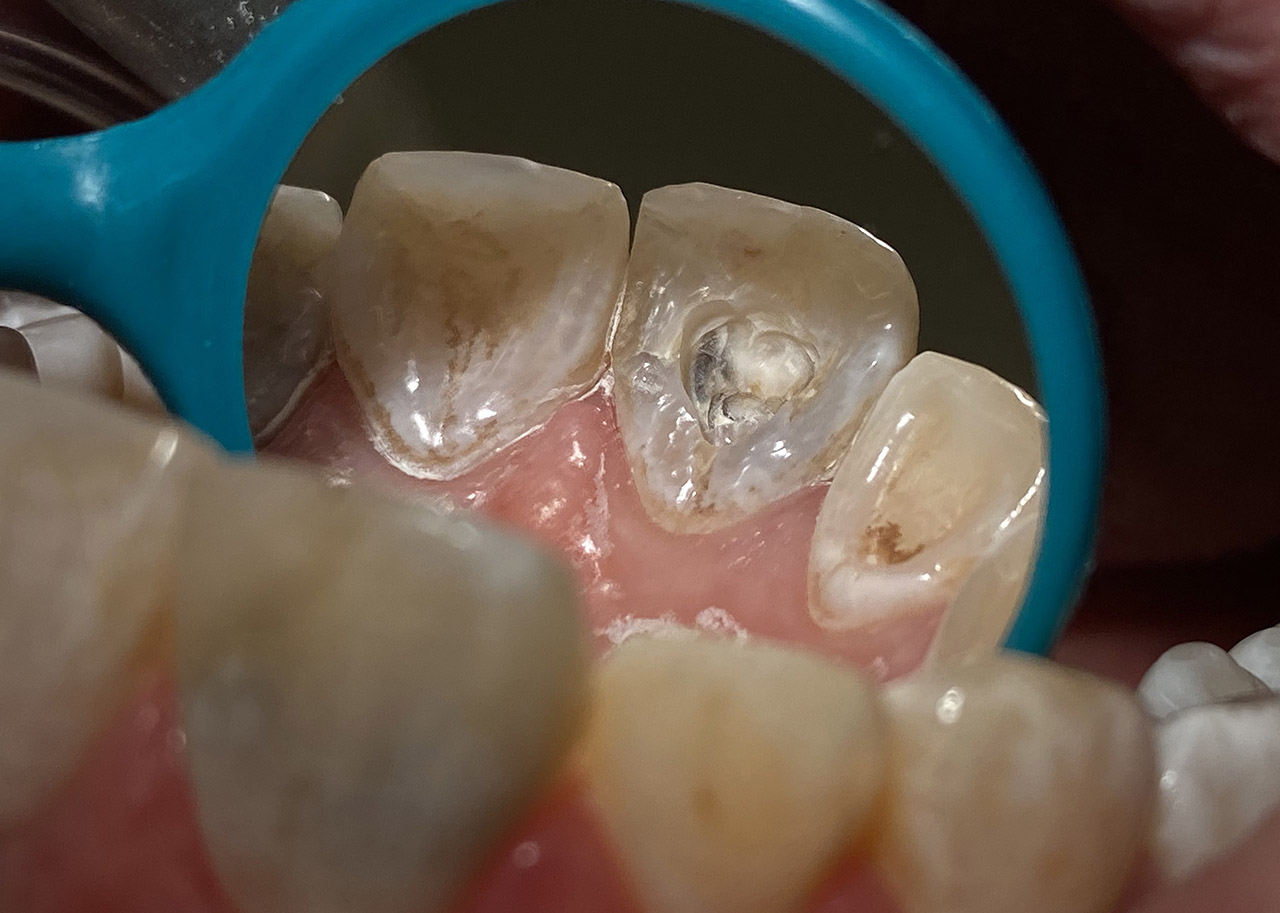

Kariestherapie:

Anamnese: tiefe Karies (Caries profunda) an beiden Oberkiefer 1. Molaren

Therapie: Zahn 16 musste Wurzelbehandelt werden, Zahn 26 konnte vital erhalten werden.

Aufbau beider Zähne in adhäsiv mit Composite/Schichttechnik.